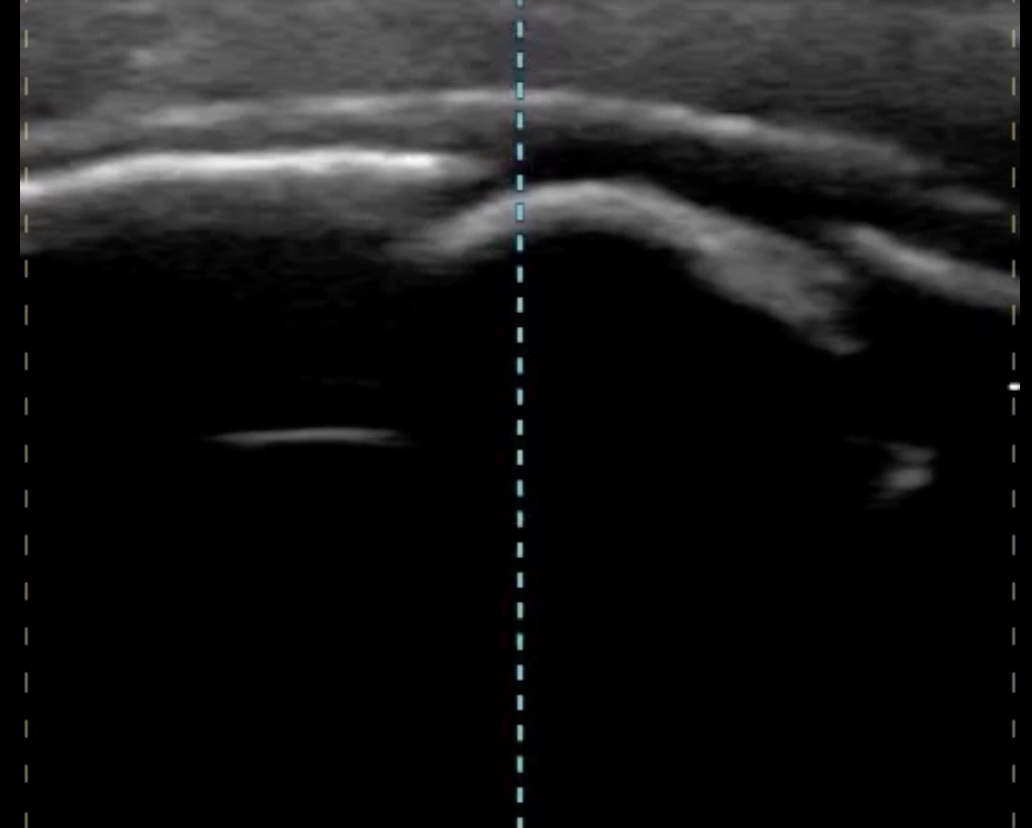

Ante nula mejoría, y retraso considerable en realización de otras pruebas complementarias. Se utiliza sonda lineal de alta frecuencia de ecógrafo portátil para valorar punto de dolor.

Hallazgos ecográficos

En la imagen se observa una disrupción de continuidad cortical ósea con aparente pérdida de esta y con aumento de la ecogenicidad en región perilesional compatible con edema.